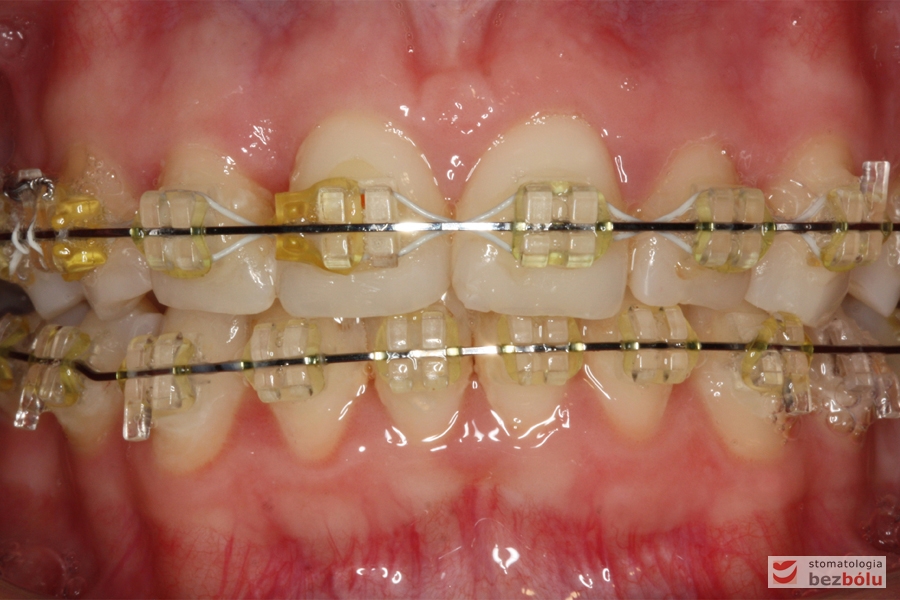

Cienkołukowy aparat estetyczny

Cienkołukowy aparat estetyczny - zastosowanie elastycznych wyciągów wewnątrzustnych

Cienkołukowy aparat estetyczny – zastosowanie elastycznych wyciągów wewnątrzustnych